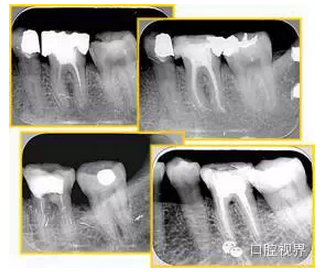

6. 鈣化

常見有修復(fù)性鈣化和增齡性鈣化。下面為根管鈣化 X 線片。

解決方法: ( 1 )清楚根管系統(tǒng)解剖形態(tài)。 ( 2 )安全頭的金剛砂鉆開髓,低速球鉆磨除鈣化牙本( ET20 ,ET40 ,DG-16 )。 ( 3 )徹底去除髓腔周壁的牙本質(zhì)齡。 ( 4 )借助化學(xué)性藥劑,如EDTA 等。